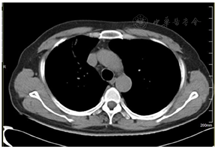

2021年7月15日复查胸部CT显示肺部感染吸收好转(图2、图3),遂停用糖皮质激素,抗生素降阶梯为头孢曲松(2 g,静脉滴注,1次/d)。BALF mNGS回报后检索惠普尔养障体感染有关文献的治疗方法亦首选头孢曲松,故继续予以头孢曲松治疗,头孢曲松治疗1周后患者病情平稳出院。院外继续长期口服甲氧苄啶磺胺甲唑(0.96 g,2次/d)治疗,停用糖皮质激素,3个月随访时患者自诉视力下降、慢性腹泻、多关节痛均得到缓解,生活质量提高。2022年3月复查胸部CT右肺上叶肺炎吸收(图4)。目前患者仍在接受口服甲氧苄啶磺胺甲唑(0.96 g,2次/d)的治疗,继续随访。